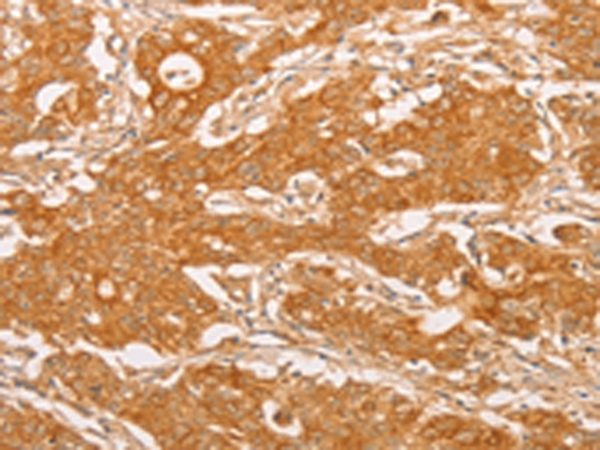

分类: 科研抗体货号: P07973别名: PIM应用: IHC反应种属: Human, Mouse, Rat